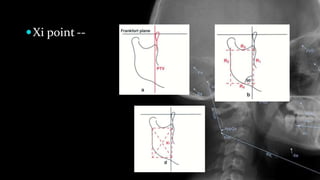

Xi point --

PLANES: